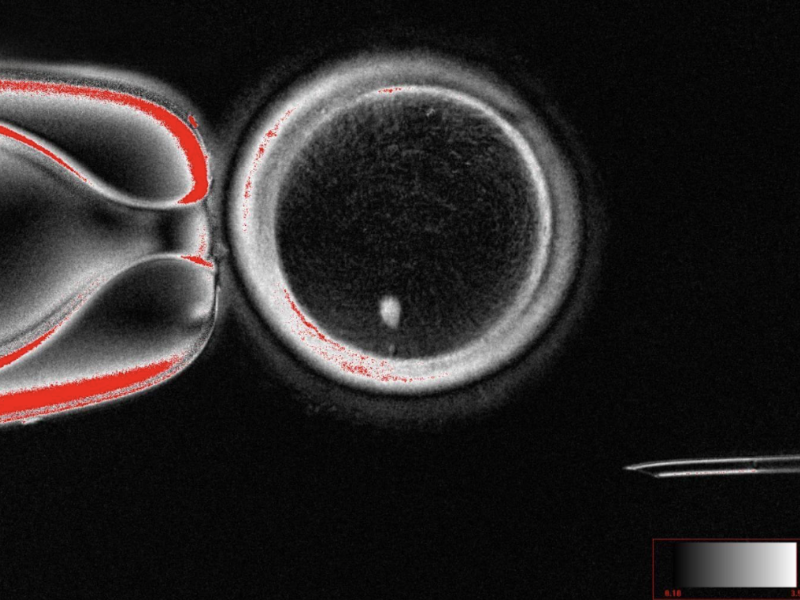

图片来源:美国俄勒冈健康与科学大学

为突破这一瓶颈,研究团队开发了名为“有丝减数分裂”的创新技术。他们将人类皮肤细胞的细胞核移植至去核的人类卵母细胞中,随后通过模拟自然减数分裂的机制,选择性丢弃一套染色体,最终获得染色体数目正常的单倍体卵母细胞。

实验中,该方法成功生成82个具备功能特征的卵母细胞。这些卵子在体外与精子结合后,约9%的受精卵发育至第6天的囊胚阶段(对应IVF治疗中胚胎移植的关键节点),但所有囊胚均未能继续发育。